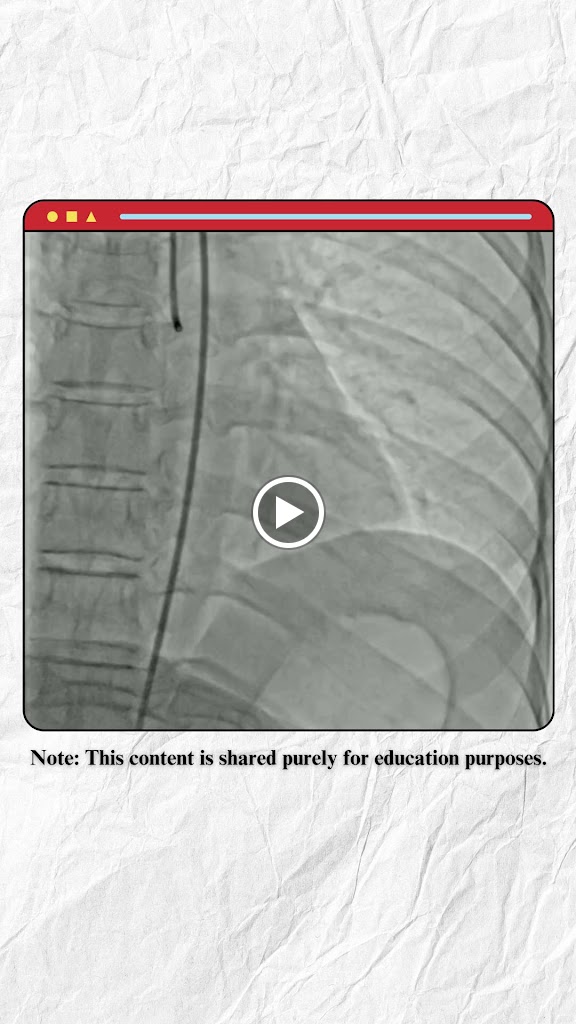

My father was admitted here for angioplasty and the angioplasty was done for free on MJPJY scheme in this hospital.